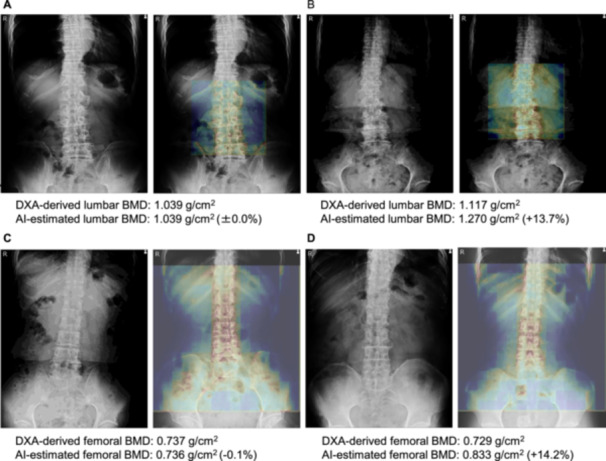

早期发现和治疗骨质疏松症和预防脆性骨折是迫切的社会问题。我们开发了一种人工智能辅助诊断系统,不仅可以根据腰椎前后位x线图像估计腰椎骨矿物质密度,还可以估计股骨骨矿物质密度。我们使用基于人群队列的腰椎x线图像评估了腰椎和股骨骨矿物质密度估计的性能以及人工智能辅助诊断系统的骨质疏松症分类准确性。人工神经网络包括深度神经网络,用于估计腰椎和股骨骨矿物质密度值,并将腰椎x线图像分类为骨质疏松症类别。通过训练双能x线吸收测量得出的腰椎和股骨骨密度值作为训练数据和预处理的x线图像的基础真值,构建深度神经网络。进行五重交叉验证以评估估计BMD的准确性。使用人工神经网络分析了来自1454名参与者的1454张x射线图像。对于骨密度估计性能,双能x线吸收测量法和人工智能估计的骨密度值之间的平均绝对误差为腰椎0.076 g/cm2,股骨0.071 g/cm2。骨量减少患者腰椎和股骨的分类表现敏感性分别为86.4%和80.4%,特异性分别为84.1%和76.3%。临床意义:该系统不仅可以对诊所或医院的患者进行骨矿物质密度的估计,还可以对普通居民的骨质疏松症进行分类。

The early detection and treatment of osteoporosis and prevention of fragility fractures are urgent societal issues. We developed an artificial intelligence-assisted diagnostic system that estimated not only lumbar bone mineral density but also femoral bone mineral density from anteroposterior lumbar X-ray images. We evaluated the performance of lumbar and femoral bone mineral density estimations and the osteoporosis classification accuracy of an artificial intelligence-assisted diagnostic system using lumbar X-ray images from a population-based cohort. The artificial neural network consisted of a deep neural network for estimating lumbar and femoral bone mineral density values and classifying lumbar X-ray images into osteoporosis categories. The deep neural network was built by training dual-energy X-ray absorptiometry-derived lumbar and femoral bone mineral density values as the ground truth of the training data and preprocessed X-ray images. Five-fold cross-validation was performed to evaluate the accuracy of the estimated BMD. A total of 1454 X-ray images from 1454 participants were analyzed using the artificial neural network. For the bone mineral density estimation performance, the mean absolute errors were 0.076 g/cm2 for the lumbar and 0.071 g/cm2 for the femur between dual-energy X-ray absorptiometry-derived and artificial intelligence-estimated bone mineral density values. The classification performances for the lumbar and femur of patients with osteopenia, in terms of sensitivity, were 86.4% and 80.4%, respectively, and the respective specificities were 84.1% and 76.3%. CLINICAL SIGNIFICANCE: The system was able to estimate the bone mineral density and classify the osteoporosis category of not only patients in clinics or hospitals but also of general inhabitants.